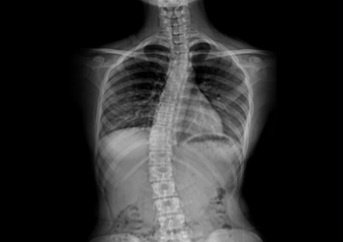

์ฒญ์†Œ๋…„์˜ 3๋ถ„์˜ 1 ์ด์ƒ์ด ๋ณ‘์ ์œผ๋กœ ํœœ ์ฒ™์ถ” ๋•Œ๋ฌธ์— ๊ณ ํ†ต์„ ๊ฒช๊ณ  ์žˆ๋Š” ๊ฒƒ์œผ๋กœ ์กฐ์‚ฌ๋˜์—ˆ๋‹ค ์ตœ๊ทผ ์„œ์šธ๋Œ€ ๋ณ‘์›์ด 3๋…„๊ฐ„ ์„œ์šธ ์‹œ๋‚ด ๋‚จ๋…€ ๊ณ ๊ต์ƒ 1,113๋ช…์„ ๋Œ€์ƒ์œผ๋กœ ์กฐ์‚ฌํ•œ ๊ฒฐ๊ณผ ์—ฌํ•™์ƒ์˜ 48%, ๋‚จํ•™์ƒ์˜ 19%๊ฐ€ ์ฒ™์ถ”์— ์ด์ƒ์ด ์žˆ๋Š” ๊ฒƒ์œผ๋กœ ๋‚˜ํƒ€๋‚ฌ๋‹ค. ๋‚จํ•™์ƒ์˜ 8%, ์—ฌํ•™์ƒ์˜ 18%๋Š” ์ฒ™์ถ”๊ฐ€ ๊ณง๊ฒŒ ์„ธ์›Œ์ง€์ง€ ์•Š๊ณ  S์žํ˜•์œผ๋กœ ํœ˜์–ด ๋ชธ์ด ํ•œ์ชฝ์œผ๋กœ ๊ธฐ์šด ๊ฒƒ์ฒ˜๋Ÿผ ๋ณด์ธ๋‹ค๋Š” ๊ฒƒ์ด๋‹ค.

์ด์— ๋Œ€ํ•ด ๋ณ‘์› ์ธก์€, ๊ณผ๋‹คํ•œ ํ•™์Šต์‹œ๊ฐ„, ์ฒด๊ฒฉ์— ๋งž์ง€ ์•Š๋Š” ์ฑ…๊ฑธ์ƒ, ๋ฌด๊ฑฐ์šด ์ฑ…๊ฐ€๋ฐฉ, ๋น„๋งŒ, ์šด๋™๋ถ€์กฑ, ์ž…์‹œ๋กœ ์ธํ•œ ์ŠคํŠธ๋ ˆ์Šค ๋“ฑ์„ ์›์ธ์œผ๋กœ ๊ผฝ์•˜์œผ๋ฉฐ ์ฒ™์ถ”๊ฐ€ ํœ˜๋ฉด ํ”ผ๋กœ๊ฐ€ ๋นจ๋ฆฌ ์™€ ํ•™์Šต ์žฅ์• ๊ฐ€ ์œ ๋ฐœ๋˜๊ณ  ์š”ํ†ต๊ณผ ๋””์Šคํฌ ๋“ฑ์ด ์ƒ๊ธฐ๊ธฐ ์‰ฝ๋‹ค๊ณ  ๊ฒฝ๊ณ ํ–ˆ๋‹ค